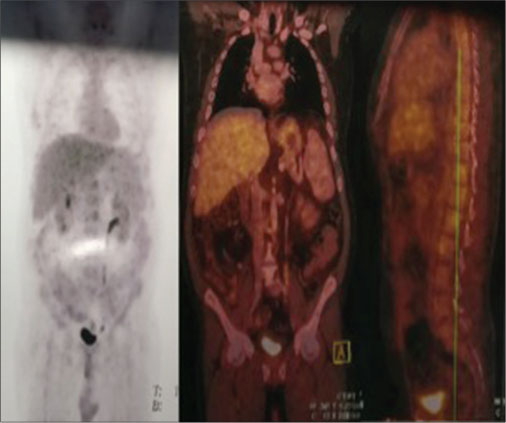

A 43-year-old male patient underwent deceased-donor liver transplantation in June 2012 for the Budd Chiari syndrome. Four years later, he presented with colicky abdominal pain. On examination, the vague nontender mass was found in the right periumbilical and iliac region. Complete blood counts showed hemoglobin of 14 gm/dl, total leukocytes count of 4900/cu mm, and platelet count of 1,89,000/mL. Liver function test revealed total bilirubin of 0.9 mg/dl with direct bilirubin-0.4 mg/dl, alanine transaminase- 64 U/L, aspartate transaminase-55U/L, alkaline phosphatase-78U/L, gamma-glutamyl transferase-78U/L, total protein-7.8 gm/dl, albumin-4gm/dl, internationalized ratio (1.4), serum creatinine-0.7 mg/dl, and blood tacrolimus level of 7 ng/ml. The patient was IgG EBV-positive. Ultrasound abdomen revealed an approximately 5.8 cm ? 3.7 cm ? 3.5 cm sized lesion composed of bowel with the asymmetrically thickened wall in the right iliac fossa. Contrast-enhanced computed tomography (CT) of abdomen revealed thickening of ileum for a length of 6 cm without obstruction. While performing colonoscopy, the distal involved part of the ileum could not be reached. Resection and end-to-end anastomosis was planned. Routine workup for surgery revealed hepatitis B positivity (which was negative before transplant). Mass which was situated about 50 cm from the ileocecal junction was removed, and jejunum to ileal anastomosis was done. Histopathology of small bowel mass showed intermediate-sized, noncleaved, lymphoid cells with high proliferation rate suggestive of Non-Hodgkin?s lymphoma of Burkitt type [Figure 1] with immunohistochemistry positive for CD 10, CD20, BCL-6, and C-myc. Tumor cells also expressed Epstein-Barr encoding region by?in situ?hybridization. They were immune-negative for CD3, MUM-1, and BCL 2. The Mib-1 proliferation index was approximately 100%. Positron emission tomography-CT (PET-CT) revealed hypermetabolic solid adrenal nodule on the left side, most likely suggestive of lymphomatous involvement. Hypermetabolic osseous foci were seen disseminated throughout axial and appendicular skeleton involving the bilateral humeri, clivus, right temporal bone, bilateral clavicles, scapulae, sternum, vertebra, multiple ribs, sacrum, pelvic bones and bilateral femora, SUVmax of reference focus in the right humerus was 22.73, most likely of lymphomatous involvement [Figure 2]. Quantitative polymerase chain reaction (PCR) for EBV revealed 2517 copies/ml. Biopsy from left iliac bone was also suggestive of BL. Bone marrow aspiration done showed basophilic cells with vacuolated cytoplasm, which was suggestive of involvement by BL. The patient was treated with chemoimmunotherapy with three cycles of rituximab, cyclophosphamide, adriamycin, vincristine, and prednisolone with intrathecal methotrexate along with tumor lysis syndrome prophylaxis. After three cycles of chemoimmunotherapy, PET-CT scan revealed complete metabolic and morphologic resolution of the left adrenal gland nodule and skeletal lesions. Very low-grade fluorodeoxyglucose uptake was seen at the sites of increased metabolic activity seen earlier in the musculoskeletal system [Figure 3].

|?Figure. 2? The positron emission tomography-computed tomography shows pathological uptake of radiotracer in bones and left adrenal gland